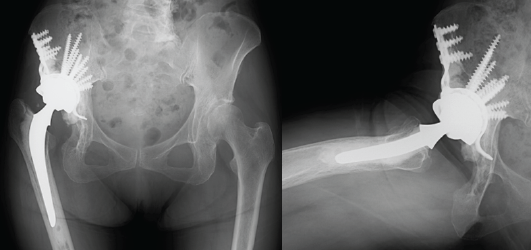

As anticipated, soft-tissue contracture obstructed the reduction of the femoral head component into the original acetabular socket. Because the hook of the reinforcement ring could not reach the obturator foramen, the acetabular floor was excavated, and the reinforcement ring was positioned more superiorly within the ilium. Due to bone fragility, bone grafting was deemed unsuitable; thus, the gap between the reinforcement ring and the acetabulum was filled with bone cement. Fifteen screws were placed into the acetabulum in all directions except the defective posterior region (Fig. 4 and 5).

Figure 5: Post-operative radiographs (left, anteroposterior view; right, lateral view).